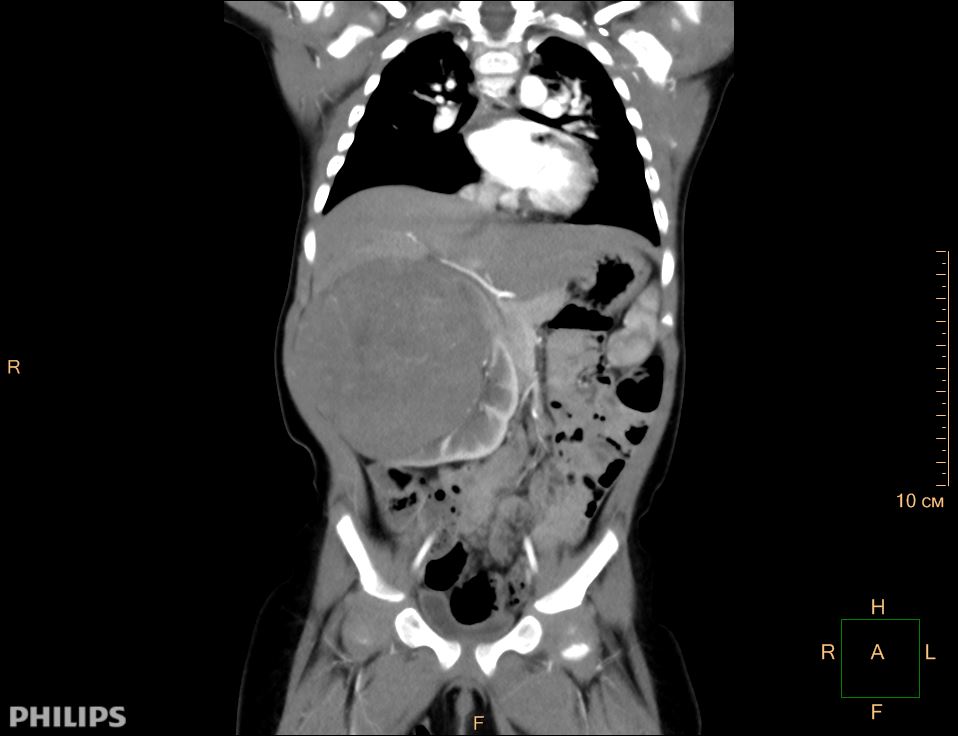

Внешне поверхность пораженного органа выглядит неровной, при разрезе можно заметить участки кровоизлияний и некроза, местами наличествуют кистообразные новообразования (в этом случае говорят о кистозной опухоли Вильмса).

Крупные опухоли можно прощупать через переднюю стенку брюшины. Может быть асимметрия живота. Большая опухоль может вызвать непроходимость кишечника. Также возможно затруднение дыхания, что обусловлено сдавливанием органов грудной клетки.

- КТ (почек, забрюшинного пространства);

- УЗИ забрюшинного пространства, брюшной полости;